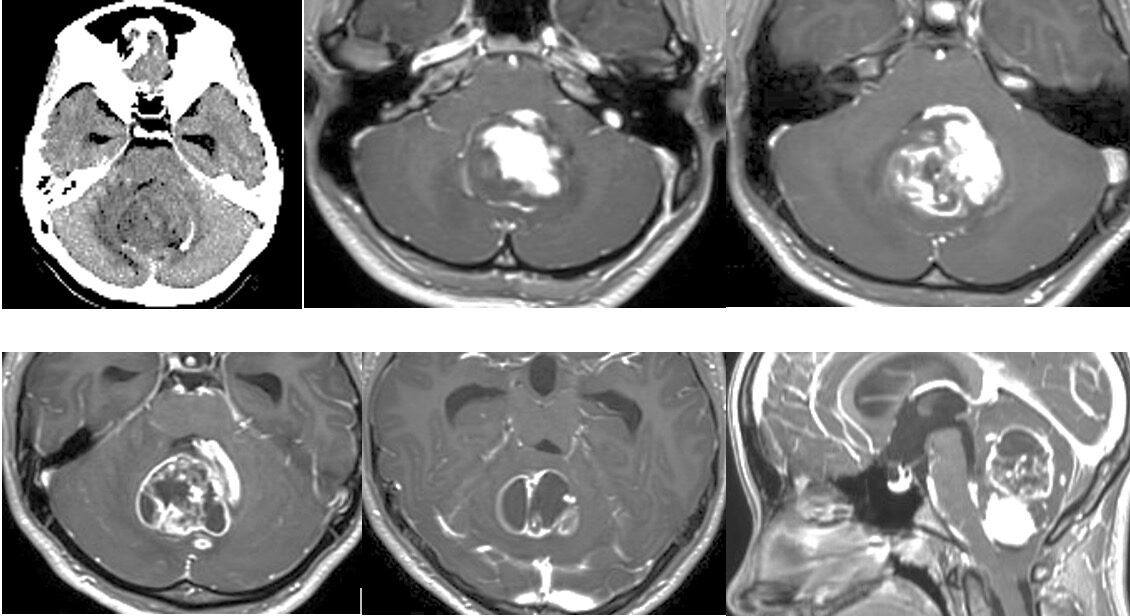

13歳小児の小脳腫瘍の摘出を行いました。術後失調や眼振が出ていましたが徐々に回復され大きな後遺症なく回復されました。よかったです。

出血の大変多い腫瘍で途中から手術に入りました。第四脳室底に癒着しておらずmedulloblastomaかと思っていましたらpilocyticでよかったです。